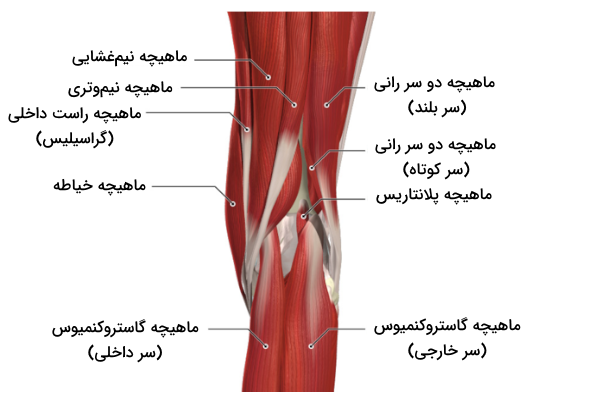

ماهیچههای اطراف زانو

ماهیچهها بافتهایی نرم هستند که از فیبرهایی با قابلیت کشسانی ساخته شدهاند. انقباض و انبساط ماهیچههای حرکتی بخشهای مختلف بدن میتواند باعث ایجاد حرکت شود. تعداد زیادی از ماهیچههای موجود در پاها حرکات زانو را کنترل میکنند، بنابراین شناخت آنها به ما در شناخت آناتومی زانو کمک میکند. ماهیچههای زانو را میتوان به دو دسته اصلی تقسیم کرد که در ادامه با آنها آشنا میشویم.

- «ماهیچههای خمکننده» (Flexors Muscles): این ماهیچهها باعث خم شدن مفصل زانو میشوند.

- «ماهیچهباشههای بازکننده» (Extensors Muscles): این ماهیچهها در جهت مخالف ماهیچههای خمکننده فعالیت میکنند و باعث باز شدن مفصل زانو میشوند.

ماهیچههای متعددی در این دو دسته قرار میگیرند که در ادامه به کمک یک جدول آن ها را نام میبریم.

| ماهیچههای بازکننده | ماهیچههای خمکننده | |

| «ماهیچه مفصلی زانو» (Articularis Genus) | ماهیچههای همسترینگ | «ماهیچه دو سر رانی» (Biceps Femoris) |

| «ماهیچه راست رانی» (Rectus Femoris) | «ماهیچه نیموَتری» یا «عضله سمی تنداینسس» (Semitendinosus) | |

| «ماهیچه پهن خارجی» یا «عضله وستوس لترالیس» (Vastus Lateralis) | «ماهیچه نیمغشایی» (Semimembranosus) | |

| «ماهیچه پهن اندرمیانی» یا «عضله واستوس اینترمدیوس» (Vastus Intermedius) | «ماهیچه گودی زانویی» یا «عضله پوپلیتئوس» (Popliteus) | |

| «ماهیچه پهن میانی» یا «عضله وستوس مدیالیس» (Vastus Medialis) | «ماهیچه خیاطه» یا «عضله سارتوریوس» (Sartorius Muscle) | |

| ـ | «ماهیچه راست داخلی» یا «عضله گراسیلیس» (Gracilis) | |

حرکات زانو

علاوه بر زمان خمیدگی زانو، امکان چرخش جانبی یا خارجی زانو در حین باز کردن آن نیز وجود دارد. در نتیجه باید گفت که مفصل زانو دارای چهار نوع حرکت است که به کمک ماهیچههای متفاوتی انجام میشود، در ادامه ماهیچههای مسئول هر حرکت را معرفی میکنیم.

- «باز شدن» (Extension): توسط «ماهیچه چهارسر ران» (Quadriceps Femoris) انجام میشود.

- «خم شدن» (Flexion): این حرکت توسط عضلات همسترینگ، گراسیلیس، سارتوریوس و پوپلیتئوس انجام میشود.

- «چرخش خارجی» (Lateral Rotation): ماهیچه دو سر رانی مسئول انجام این حرکت است.

- «چرخش داخلی» (Medial Rotation): پنج ماهیچه نیموتری، نیمغشایی، گراسیلیس، سارتوریوس و پوپلیتئوس مسئول این حرکت هستند.